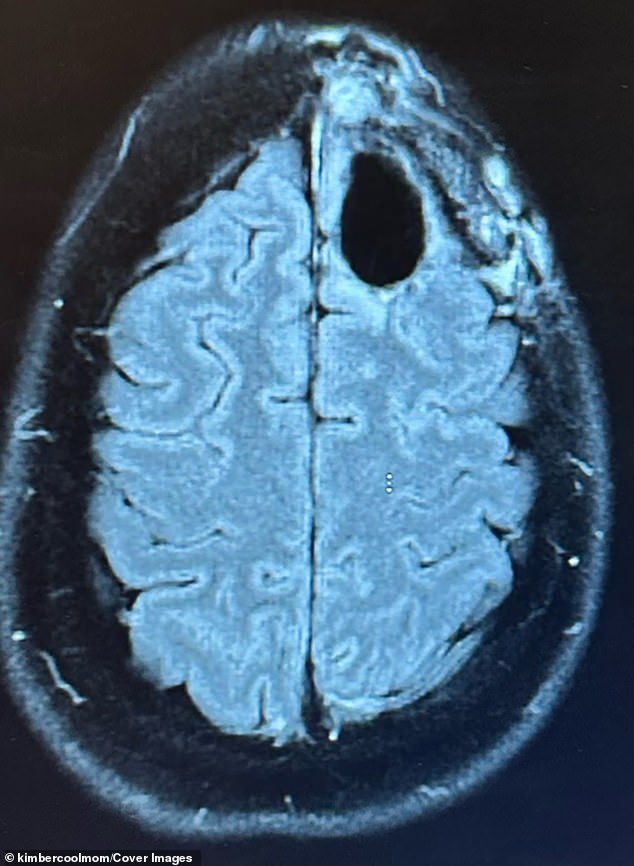

Pelling's journey began with sudden night terrors, crushing fatigue, and persistent brain fog. When her family doctor suspected seizures, she was rushed to the hospital for an MRI, which revealed a lime-sized tumor in her frontal lobe. A biopsy confirmed the worst: a grade-four astrocytoma, a cancer with a median survival rate of around 31 months. The prognosis was grim, but Pelling refused to accept it. 'I have babies at home. I can't leave them,' she said. 'But I felt this quiet voice telling me not to give up.'

Conventional treatment followed. Pelling endured surgery to remove the tumor, followed by five weeks of radiation and months of chemotherapy. The regimen left her bedridden, battling fatigue, hair loss, and brain fog. For a time, scans showed no signs of cancer, offering a fleeting glimmer of hope. But eight months later, a new, inoperable tumor appeared, and her prognosis was reduced to just one year. Faced with this reality, Pelling made a difficult decision. In August 2023, she halted conventional treatment and turned to alternative protocols, determined to fight the disease on her own terms.

In 2025, Pelling returned for a routine brain scan, bracing herself for the worst. The results were unexpected: no evidence of cancer. 'Hearing there was no evidence of cancer felt surreal,' she said. 'I just kept saying